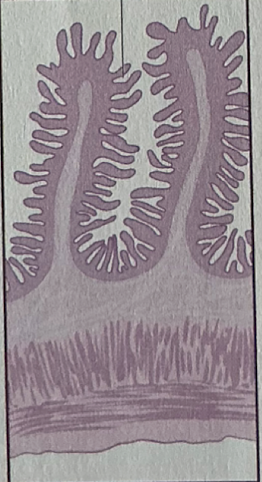

duodenum

jejunum

iluem

colon

duodenum

duodenum

________ receives chyme when stomach empties; exocrine release site for gallbladder & pancreatic secretions

intestinal glands

secrete mix of sucrase, maltase, & peptidases + definsins & enzymes

brunner’s glands

produce mucus-rich alkaline secretion to protect from acidic content, lubricate walls, & enable absorption

jejunum

jejunum

mid segment of SI, function in absorption

ileum

last part of SI, absorption of vitamin B12 bound to intrinsic factor